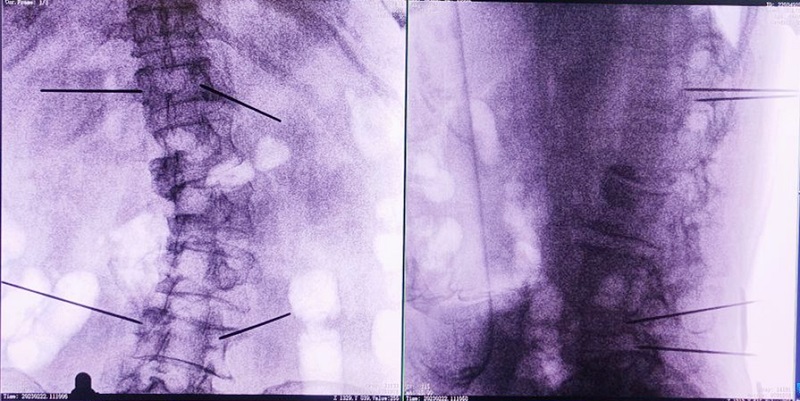

(4)所有引导针植入完毕后,沿引导针方向进行椎弓根及椎体置管,建立通道;

(5)沿通道注入骨水泥,恢复椎体高度,并观察其扩散情况,达到满意效果后,停止注入骨水泥。